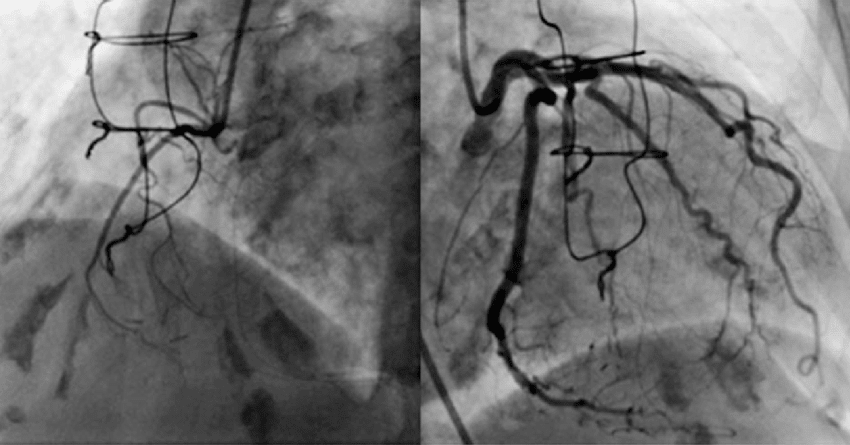

A continuación, detallamos algunos de nuestros estudios realizados en nuestro servicio

Es un procedimiento mínimamente invasivo para diagnosticar obstrucciones en el flujo de sangre que circula por las arterias coronarias.

Las obstrucciones en las arterias coronarias pueden provocar angina de pecho o un infarto de miocardio, por lo cual el resultado de este estudio puede conducir a la realización de una angioplastia, la colocación de un stent

La cinecoronariografía o cateterismo cardíaco consiste en la introducción de un tubo delgado (catéter) a través de una arteria hasta llegar al nacimiento de las arterias coronarias. Tras inyectar un líquido de contraste yodado, un equipo especial de rayos x permite ver la luz de las arterias coronarias y determinar dónde hay una obstrucción causada por una placa de colesterol o un coágulo.